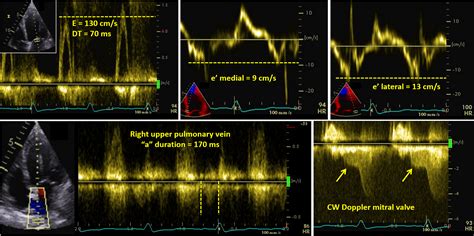

e to e prime ratio